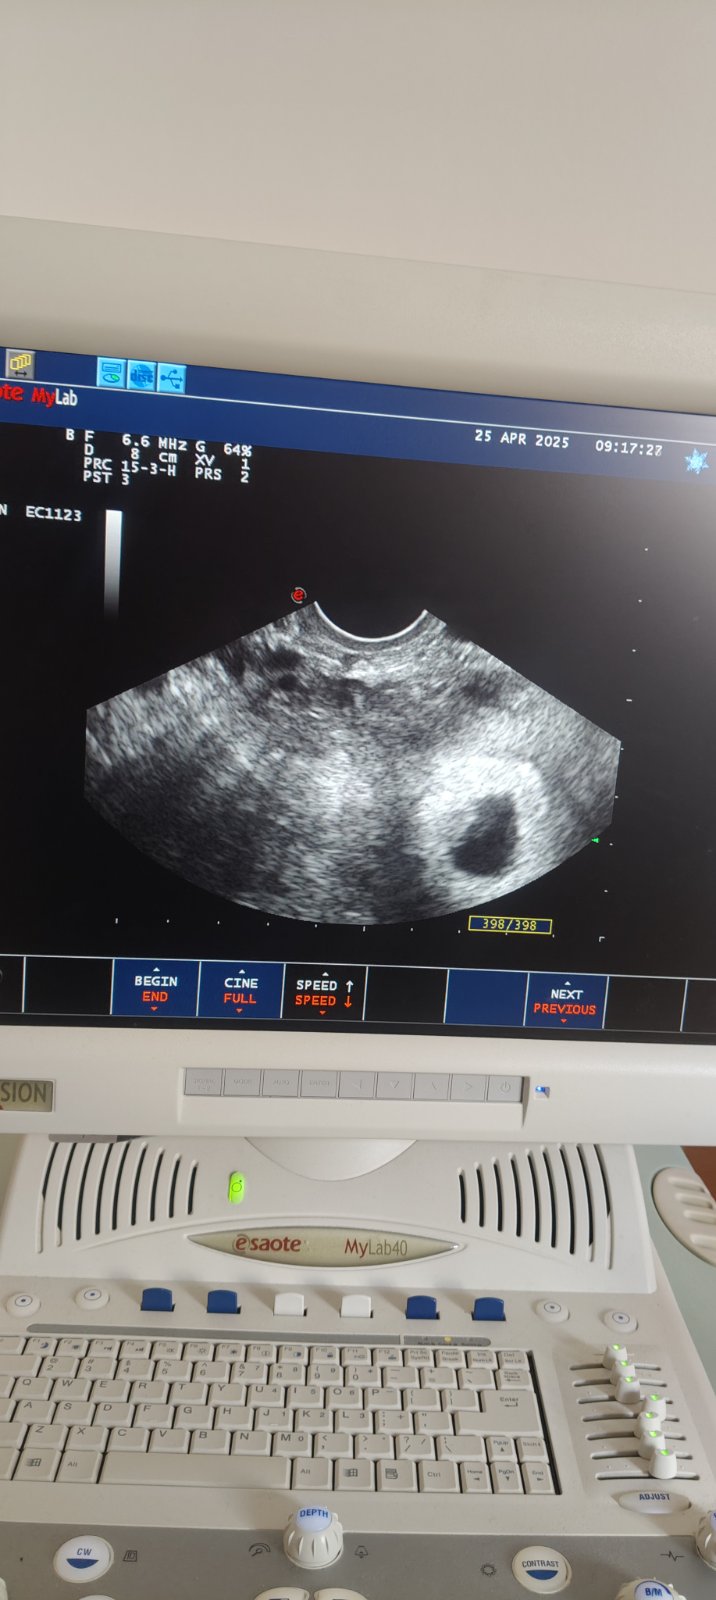

Odborné rady k ultrazvuku z ôsmeho týždňa tehotenstva

povedala, ze je vsetko ok, podla vysledkov krvi 8 tyzden, len ja mam vnutorne zvlastny pocit

Vidim co tam je, ale nebudem sa k tomu vyjadrovat uz len z dovodu, ze ta fotka je priserne rozmazana, takze nijake relevantne hodnotenie k tomu nebudem pisat.

@colsami lekar bol zastupujuci lekar, vyjadril sa len tolko ze ano je tu a zije, nic viac, preto som znepokojena a hladam aj takto pomoc, som mimo SR momentalne

@colsami môžem sa Ťa ešte opýtať čo si myslela tým že vidíš čo tam je ? Ďakujem pekne